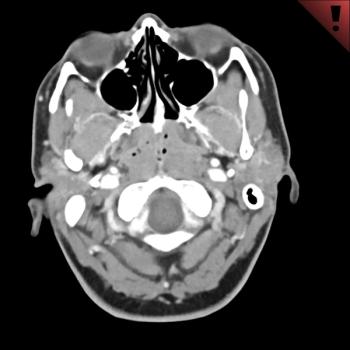

Patient presents with right facial swelling.